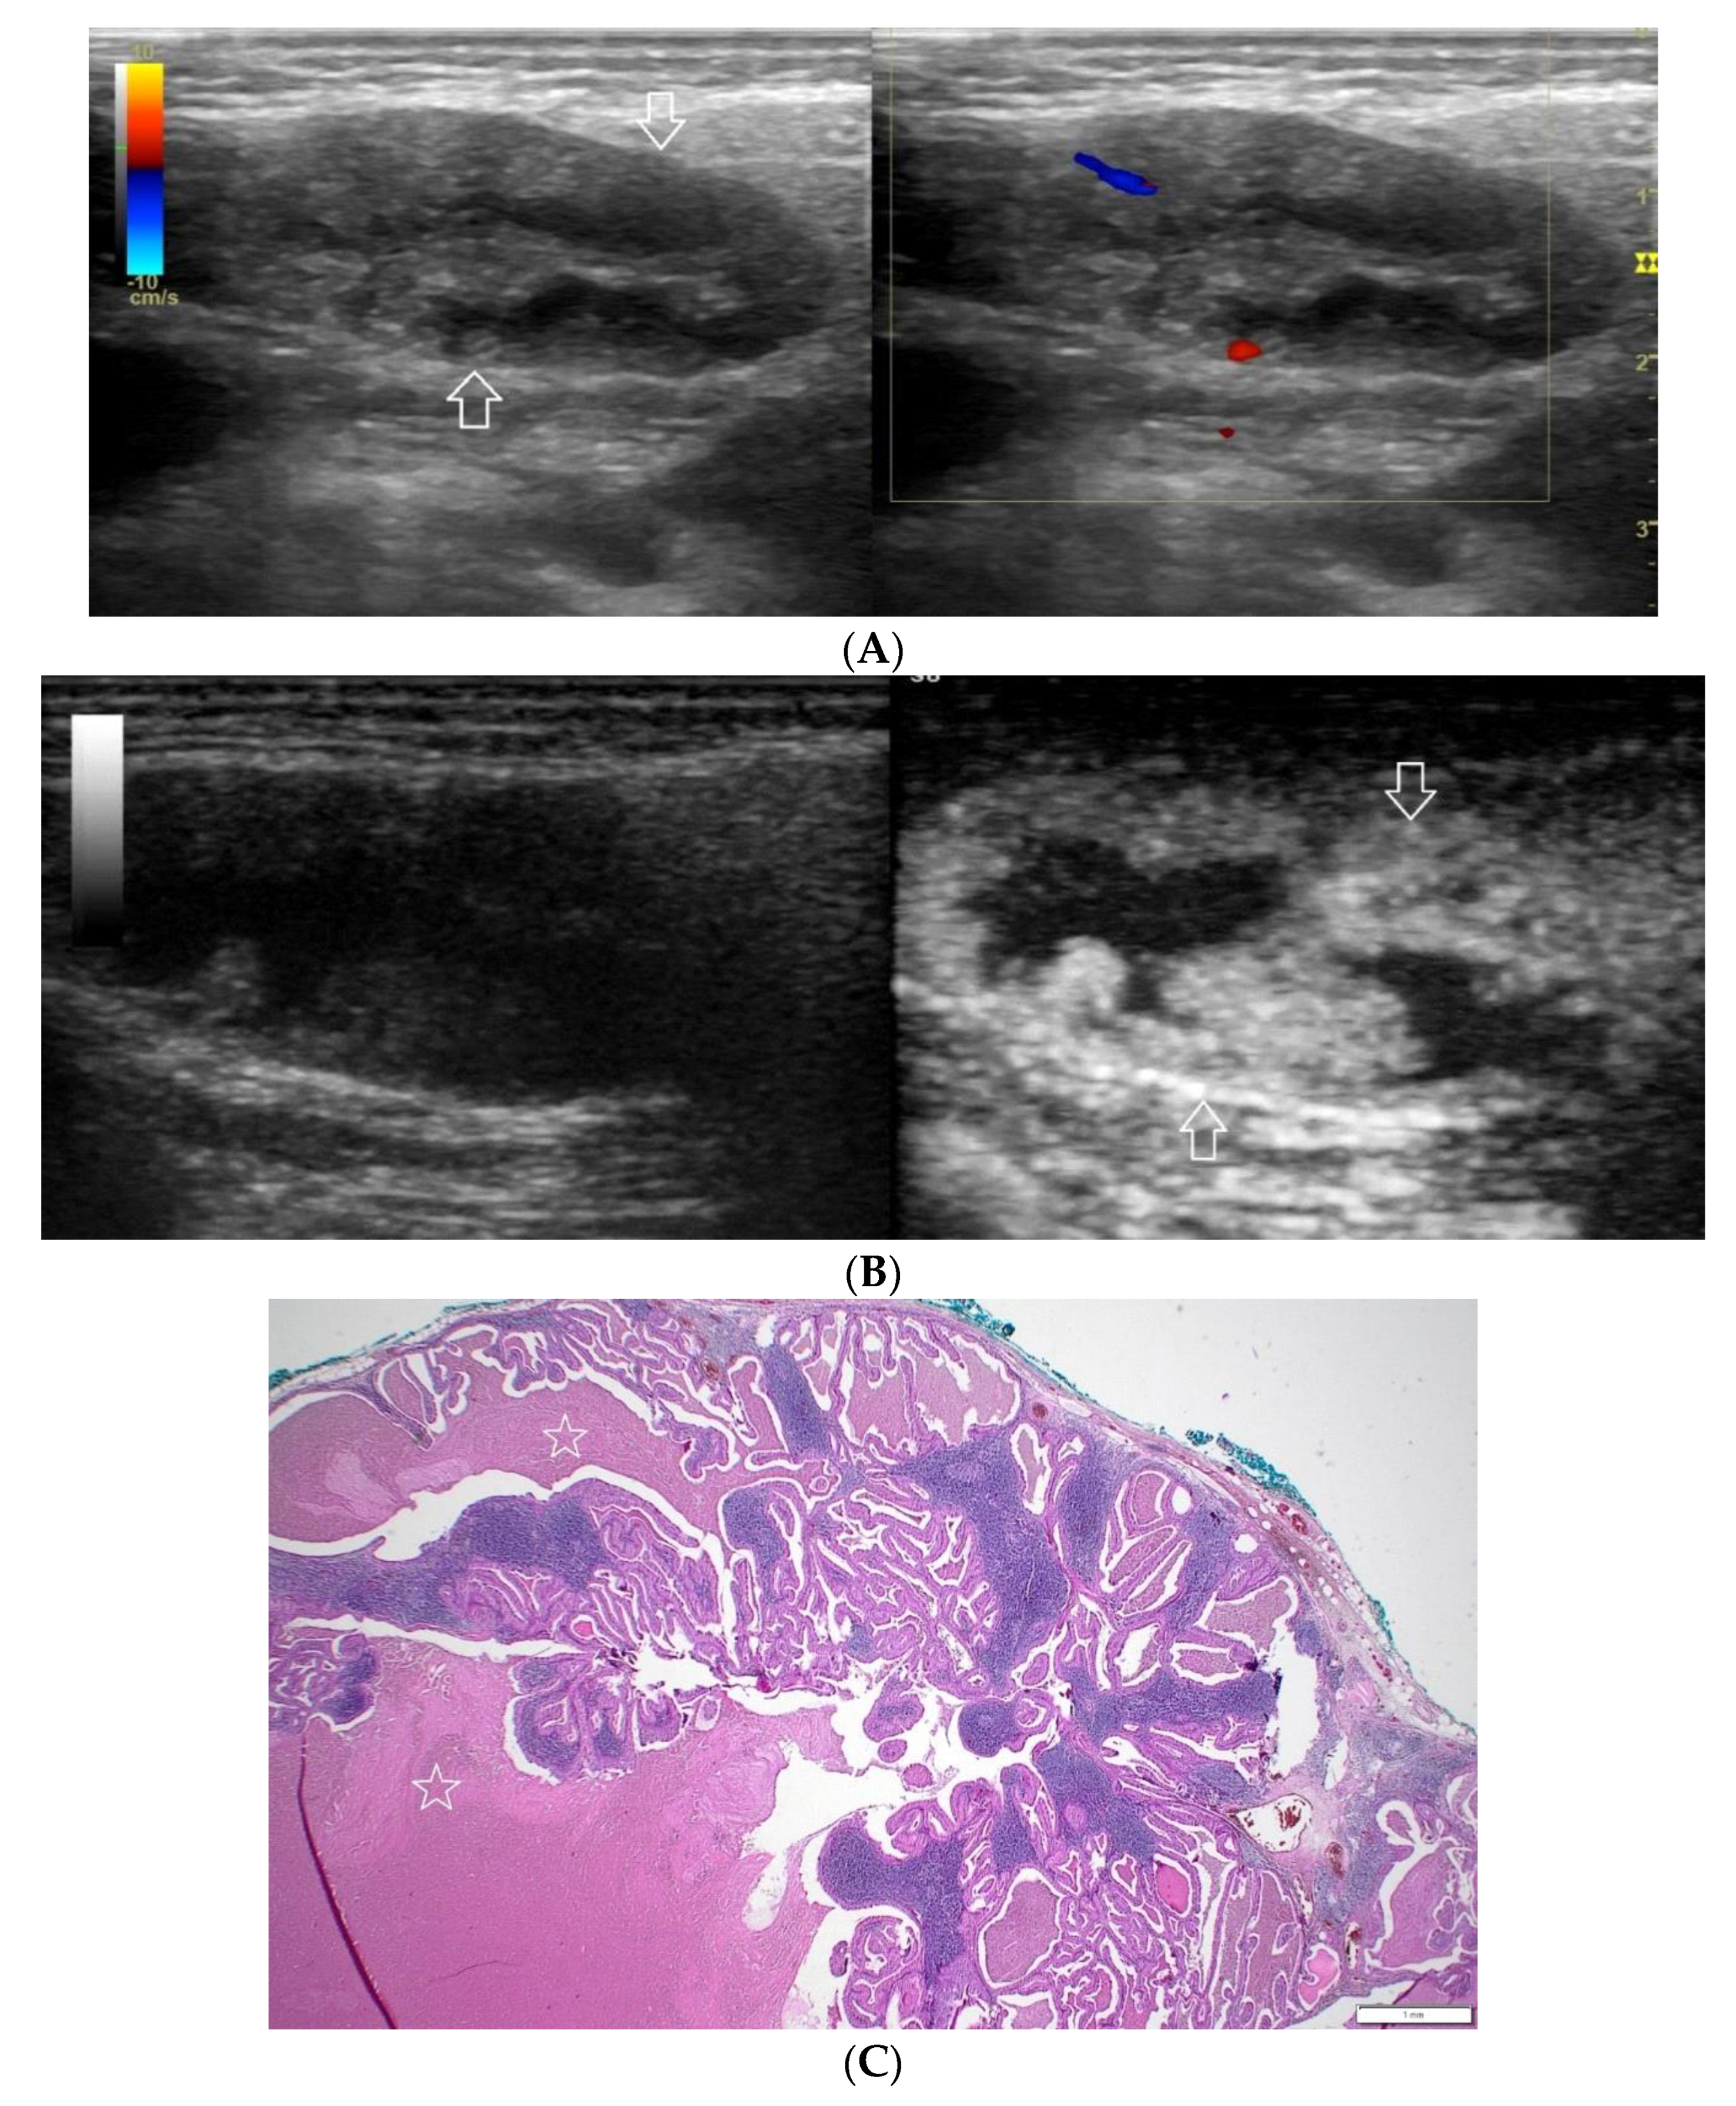

Figure 5.

(A−C) Warthin’s tumour. (A) Routine ultrasonographic examination in B presentation and colour Doppler: a small multi-arched hypoechogenic, well-demarcated focal lesion of a heterogeneous echostructure. On CD, low blood flow is observed. (B) Contrast-enhanced imaging in arterial phase: a strong homogeneous enhancement of a peripheral part of the lesion (white arrows). A weakly enhanced central part. (C) Pathomorphological image, H & E stain. Large areas of irregular shape containing fluid (white stars). A part containing glandular tissue located peripherally. Black star indicates a lymph node.

A correlation between professional photographs of CEUS imaging and those of microscope slides containing postoperative specimens was observed. It appears that the strong heterogeneous enhancement pattern is more likely to occur in benign lesions, while malignant, and malignant potential lesions tend to present weak heterogeneous enhancement. The foundation of such tendencies is revealed in pathomorphological specimens. Various tissues such as fluid and cartilage commonly present in salivary gland tumours, are generally poorly enhanced. The enhancement of such areas in CEUS is poor if any. The cross-section of Warthin tumour, for example, is presented by one or more often numerous minor cysts containing mucus.

Those not-enhanced areas and structures revealed on histopathological photographs overlapped (Figure 1, Figure 2, Figure 3, Figure 4, Figure 5 and Figure 6).